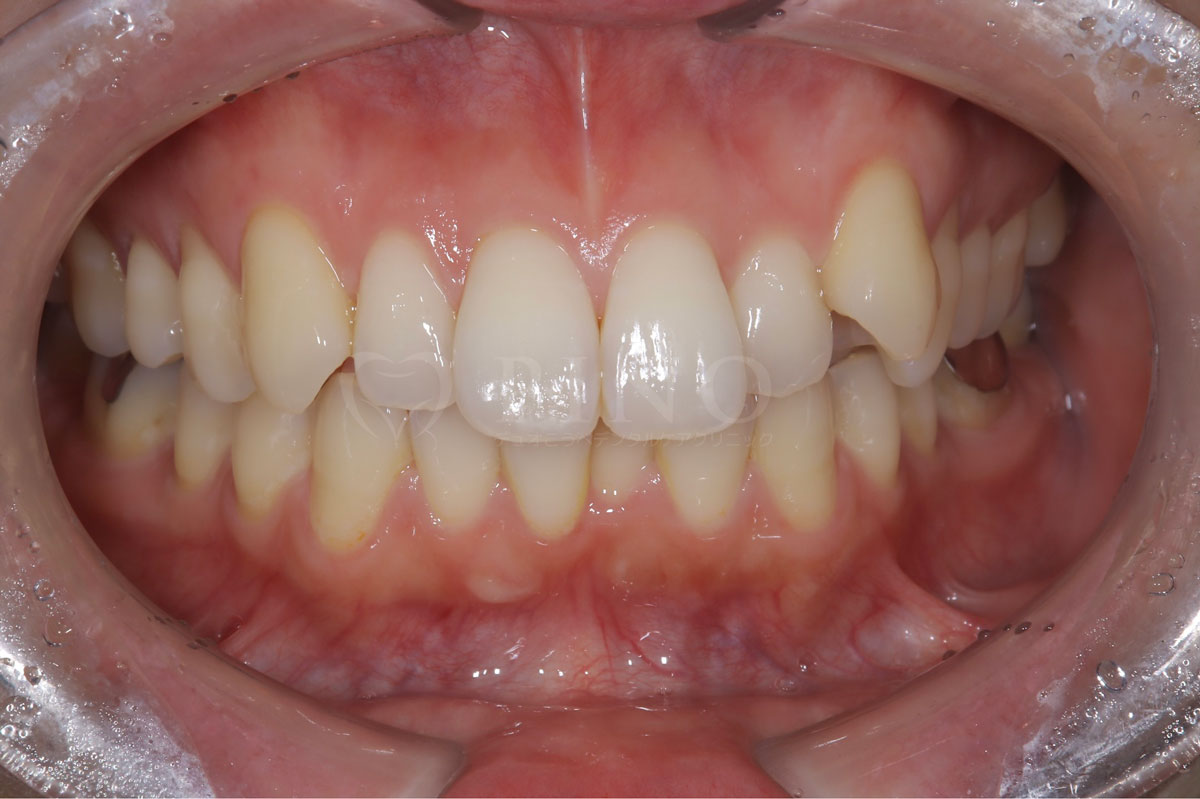

症例9:歯が全体的にガタガタして気になる(30代女性)

主訴 歯が全体的にガタガタして気になる 診断名 上下顎1級叢生 治療方法 マウスピース全顎矯正 抜歯 あり4本 オルソパルス なし 治療期間 1年8ヶ月 費用 749,000円 副作用・注意点 歯を抜く際に痛みを伴う可能性がある、矯正後後戻りを防ぐためリテーナーの使用が必要となる 備考 ホワイトニングも並行して行った -